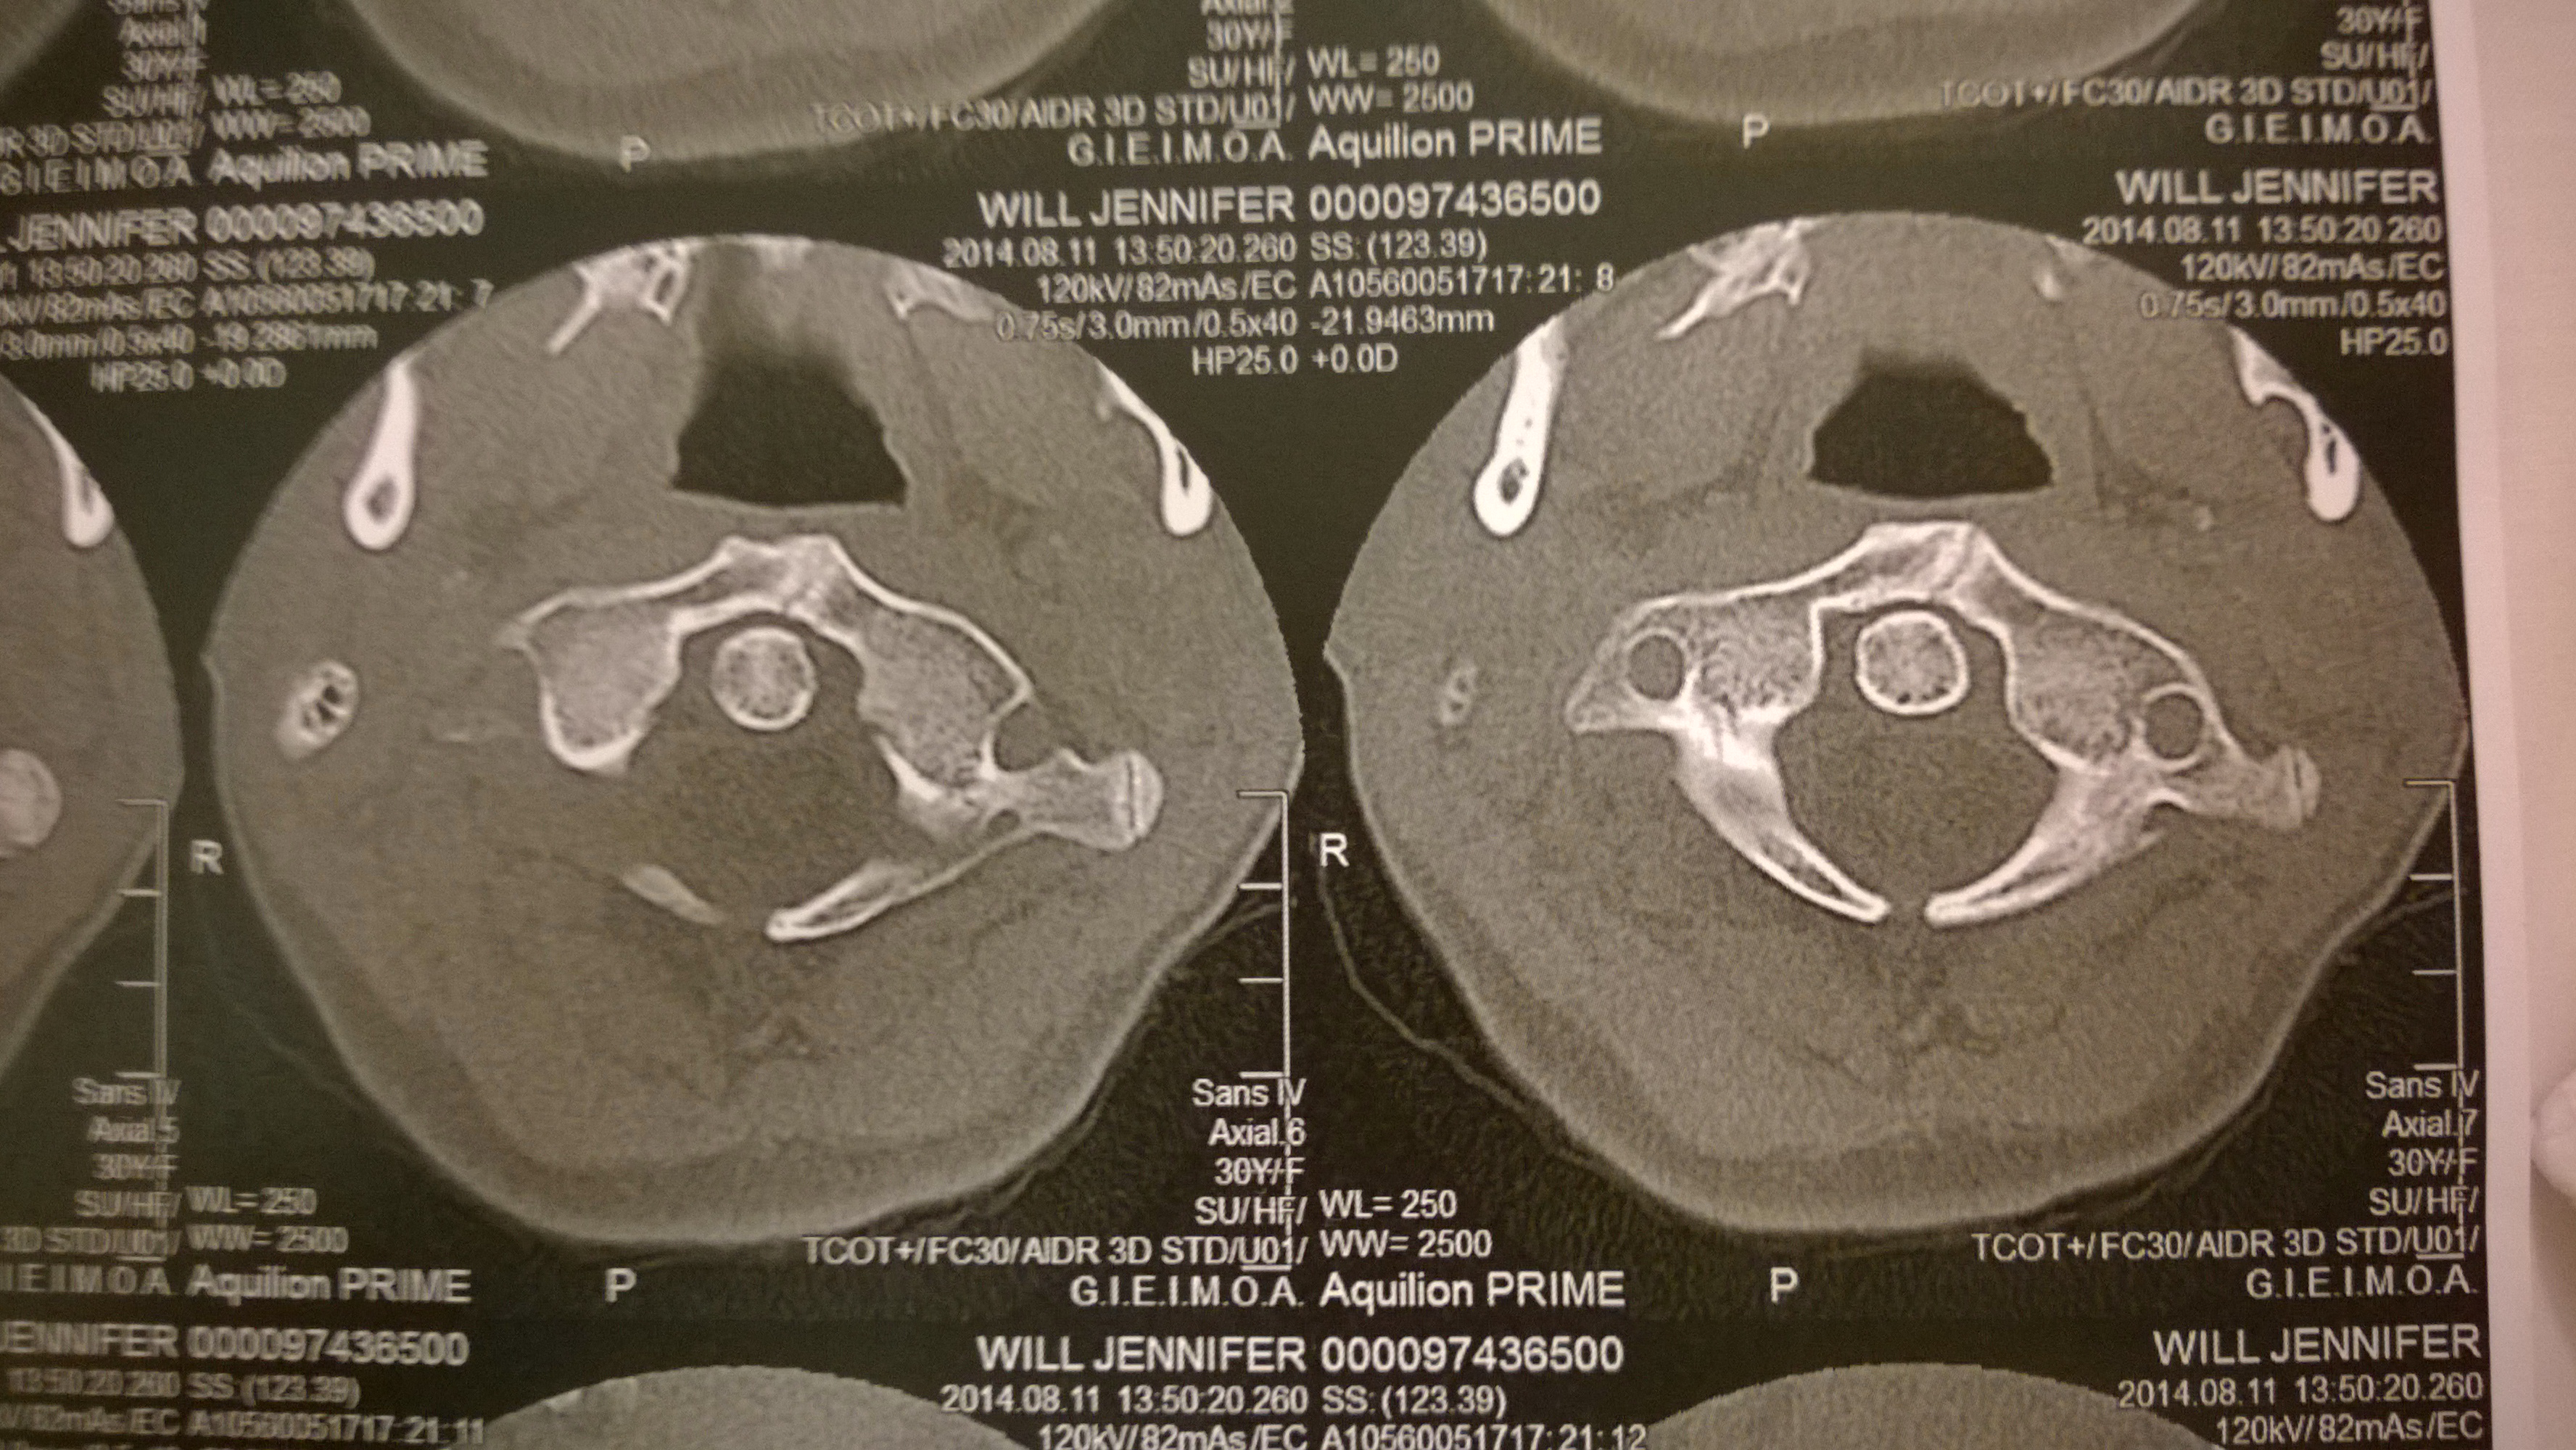

När jag var ca 20 var jag så dålig i ryggen att jag inte kunde arbeta och var sjukskriven. Efter många läkarbesök, höga doser värkmedicin så blev jag remitterad till Röda korsets sjukhus för utredning. Först sa man mest att all min värk berodde på min tragiska barndom, men sen gjorde man något som man inte gjort innan en vad man då kallade för ”provokations röntgen” där man tydligt kunde se att jag har en skolios men också en mekanisk bäckendysfunktion. Jag fick olika korsetter för bäcken, rygg och nacke men kände mig inte bättre utan snarare sämre. Det sista de kunde erbjuda var till slut en steloperation, som jag tackade nej till. Så jag tackade för mig och sökte andra jobb inom hälsosektorn i jakt på hur man kan rehabilitera sig själv.